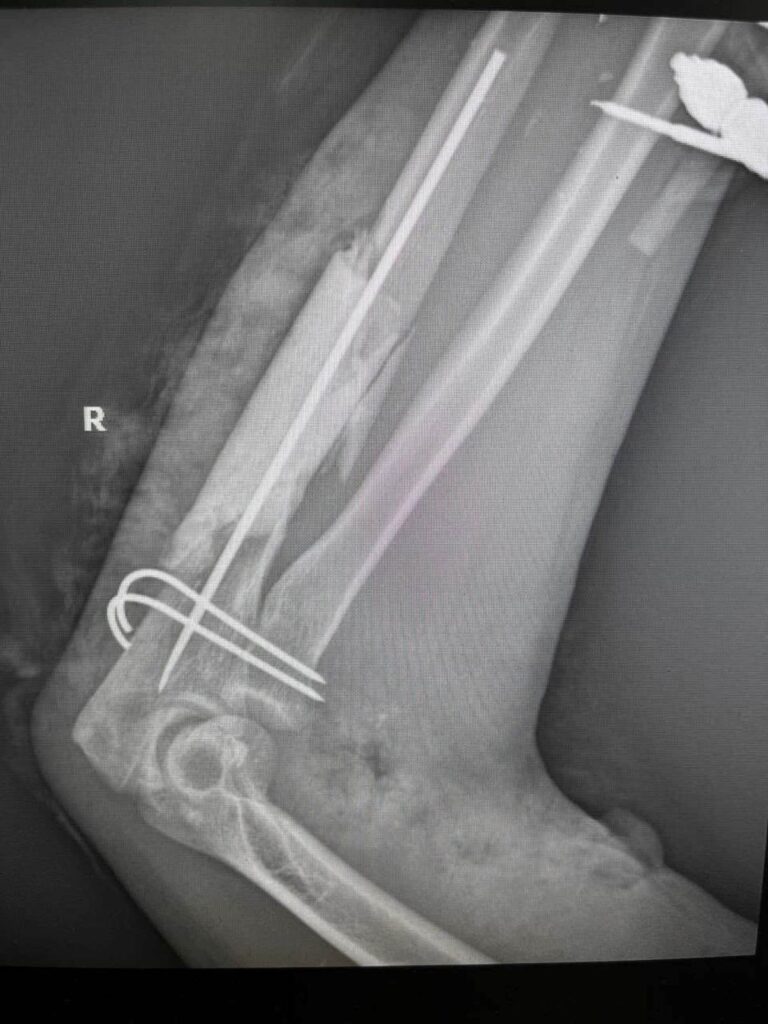

Часть локтевой кости раздроблена и лишена признаков жизни, головка лучевой кости в вывихе… Переломы костей запястья и отдельных фаланг.

Неживую часть локтевой кости пришлось выбросить и заменить костным цементом (на снимке это хорошо видно).

Головка луча удерживается спицами (при «мирных» переломах этого не нужно; а вот в таких случаях, когда всё разрушено вокруг – приходится), на руку наложен аппарат. Впереди еще несколько операций «чистки» и кожной пластики.